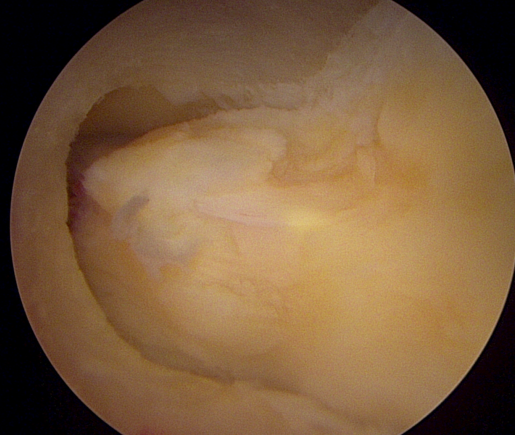

양방향 척추 내시경을 통한 다발성 척추 협착증의 치료 [온종합병원 척추센터 우영하 소장 ]

척추관 협착증은 척추관이 좁아지거나 협착되어 척수나 신경근을 압박하는 상태를 말합니다. 이런 경우, 양방향 척추 내시경이 매우 유용한 치료 수단이 될 수 있습니다.

- 계획: 양방향 척추 내시경은 미세한 카메라와 도구를 사용하여 척수와 주변 신경 구조를 정밀하게 시각화할 수 있습니다. 이를 통해 정확한 진단을 내릴 수 있으며, 각 환자에게 맞는 개별적인 수술 계획을 수립할 수 있습니다.

양방향 척추 내시경은 척추관 협착증과 같은 척추 질환의 치료에 있어서 현대적이고 효과적인 접근법 중 하나로 인정받고 있습니다.